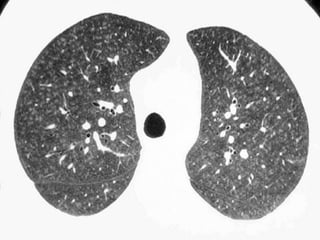

The Many ‘HRCT Faces’ of NSIP

Honeycombing not

a

prominent feature

!!!!